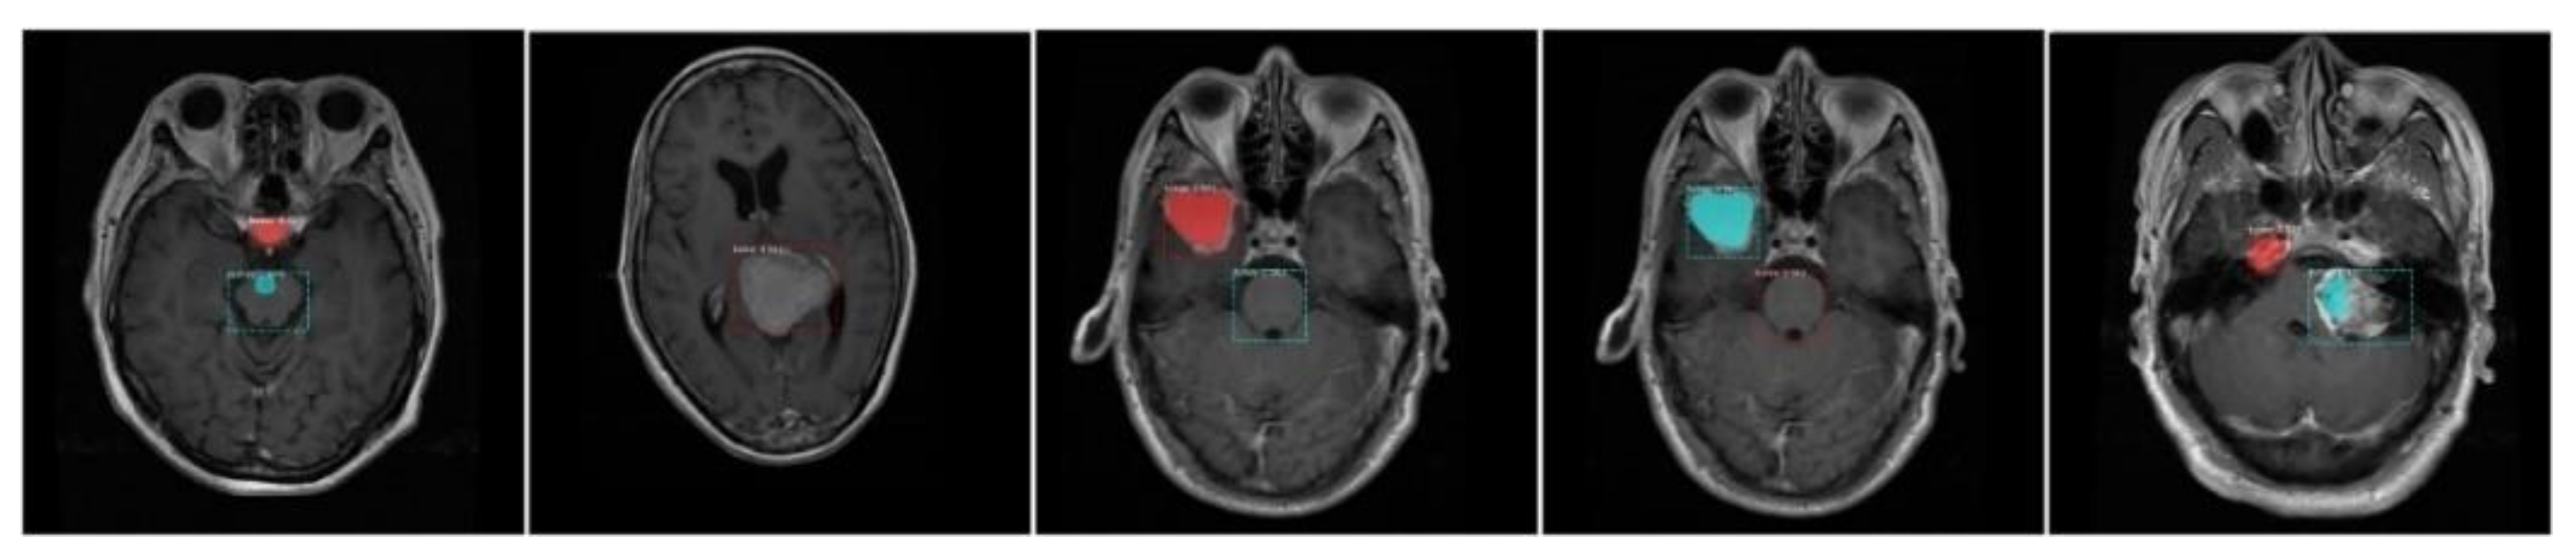

- We have created the annotations which are essential for the training of the proposed model because available datasets do not have a bounding box and mask ground truths (GTs).

3.2. Annotations